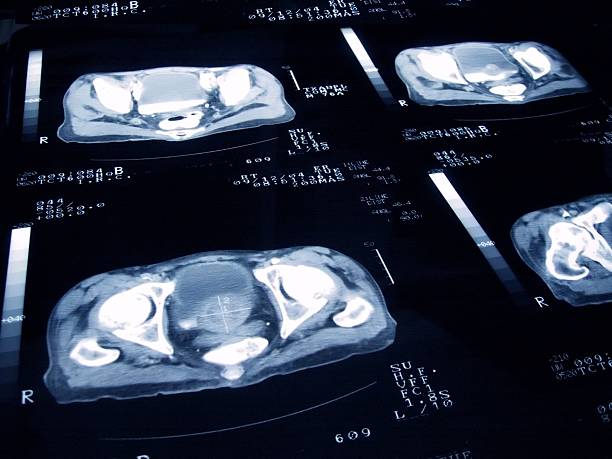

담낭염은 담즙을 저장하는 담낭에 염증이 생기는 질환으로, 대부분 담석(담낭결석)으로 인해 발생합니다.

담낭염은 급성과 만성으로 나뉘며, 급성 담낭염은 심한 통증과 함께 응급 상황으로 이어질 수 있습니다.